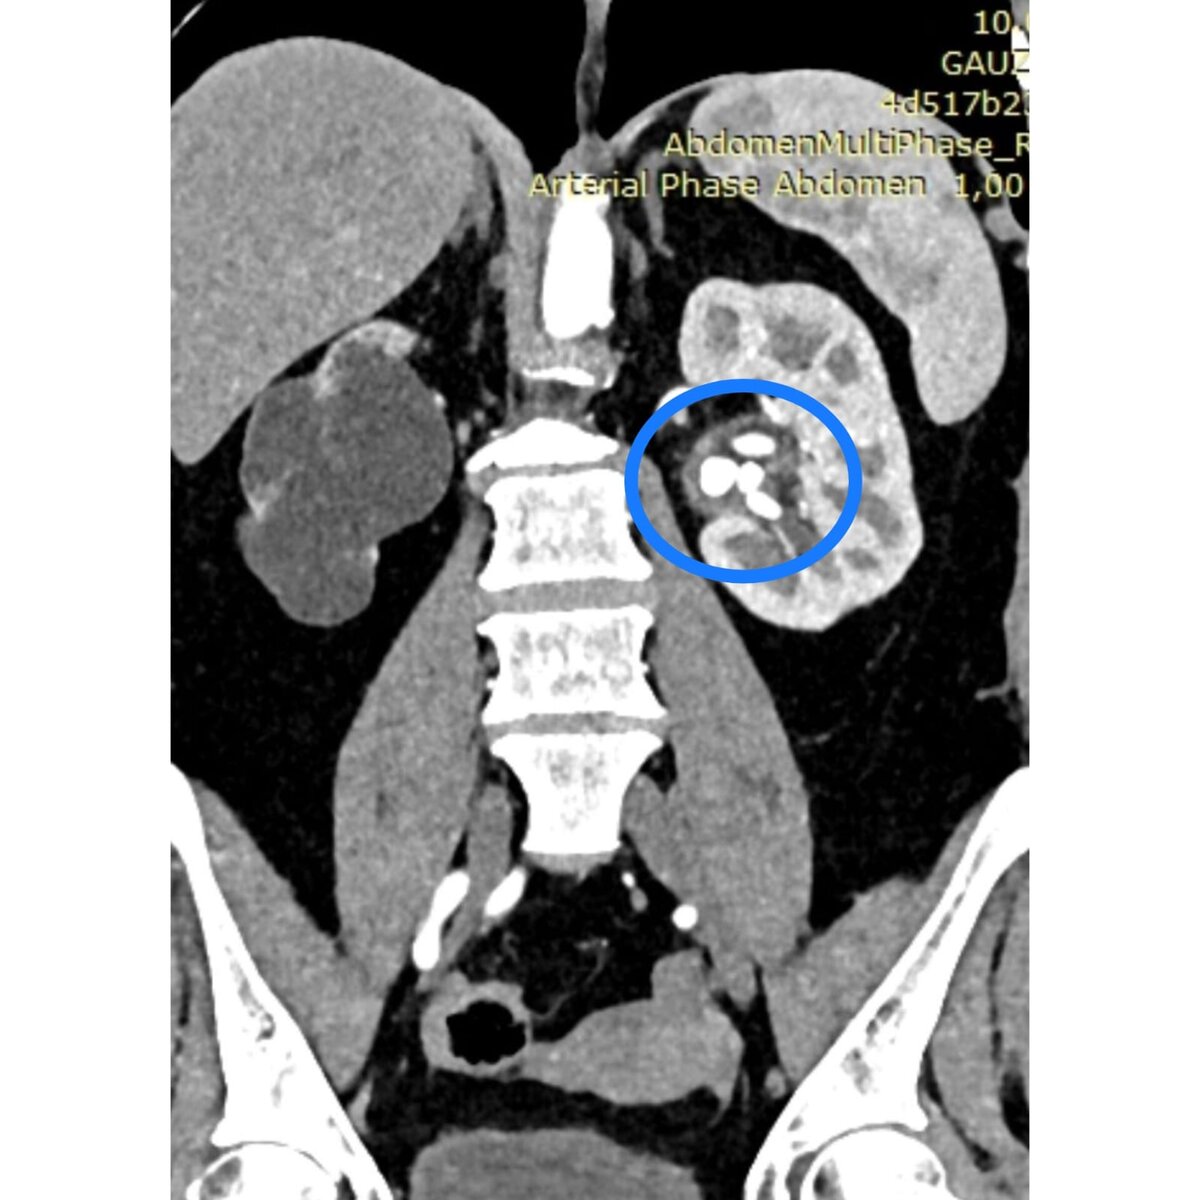

Урологи Томской ОКБ и клиник Сибирского государственного медицинского университетов провели совместную сложную операцию, в ходе которой им удалось через мини-доступ 5 мм раздробить семь крупных камней в единственной функционирующей почке у пациентки из Анжеро-Судженска Кемеровской области. Летом 2023 года женщина обратилась в клиники СибГМУ с сильными болями в области спины. В результате обследования оказалось, что причиной стали множественные камни в почке – всего семь камней, самые крупные из них были размером с орех - около 2,5 см. Эта почка была единственная функционирующая, вторая – уже несколько лет не выполняет свои функции.

Летом 2023 года женщина обратилась в клиники СибГМУ с сильными болями в области спины. В результате обследования оказалось, что причиной стали множественные камни в почке – всего семь камней, самые крупные из них были размером с орех - около 2,5 см. Эта почка была единственная функционирующая, вторая – уже несколько лет не выполняет свои функции.

Множественные камни в почке на снимке КТ